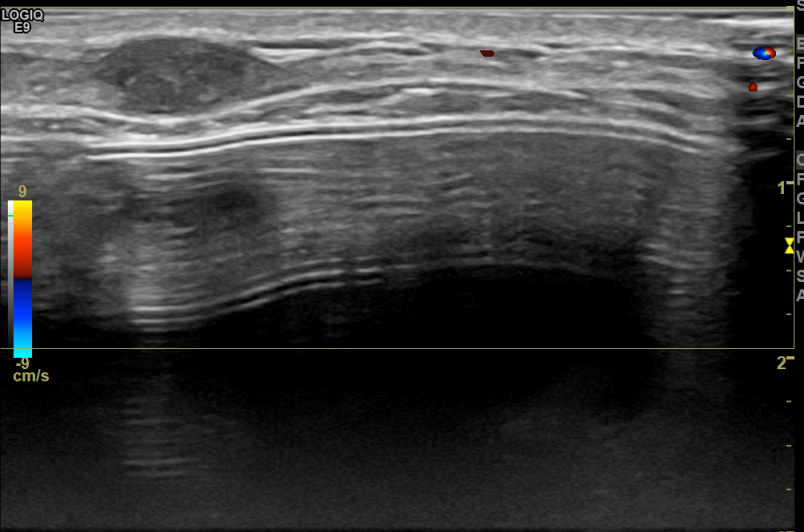

상기환자는 만져지는 멍울로  내원하신 40대초반

여성분으로 의심스러운 우측혹 조직검사 시행해 상피내암으로 진단되었습니다